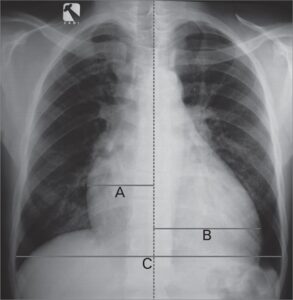

Mediastino ûˋ um espaûÏo no meio do tû°rax entre a pleura de cada um dos pulmûçes e se estende do esterno atûˋ a coluna vertebral (ûÂntero-posterior). û dividido em superior e inferior obedecendo o pericûÀrdio.